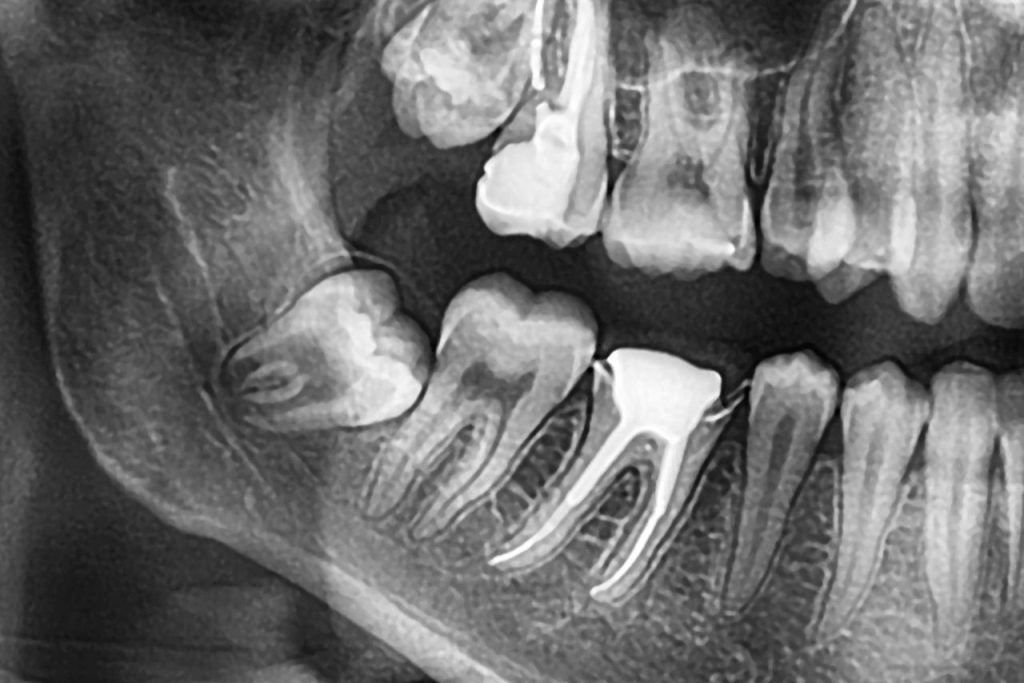

Le traitement de canal, souvent redouté par de nombreux patients, est en réalité une procédure essentielle pour préserver vos dents. Mais qu’est-ce que c’est exactement ? En termes simples, le traitement de canal consiste à retirer la pulpe dentaire infectée ou endommagée, de nettoyer l’intérieur de la dent et de sceller la chambre pulpaire. Ce processus permet non seulement de soulager la douleur, mais également de sauver une dent qui, sans intervention, pourrait nécessiter une extraction.

Le traitement de canal permet de sauver une dent en retirant le nerf affaibli ou infecté, ce qui évite d’avoir recours à l’extraction de la dent.

La séance commence généralement par une anesthésie locale pour assurer votre confort. Notre dentiste procédera ensuite à l’ouverture de la dent pour accéder à la pulpe. Après avoir retiré celle-ci, chaque canal sera nettoyé, décontaminé et rempli avec un matériau spécial appelé gutta-percha. Enfin, la dent sera scellée avec une couronne ou un plombage, selon l’étendue des dégâts.